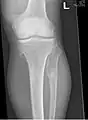

El diagnóstico de HMO se basa en establecer una correlación precisa entre las características clínicas mencionadas anteriormente y las características radiográficas características. Los antecedentes familiares pueden proporcionar una pista importante para el diagnóstico. Esto se complementa con pruebas de los dos genes en los que se sabe que las variantes patogénicas causan HMO, a saber, EXT1 y EXT2. Una combinación de análisis de secuencia y análisis de deleción de todas las regiones codificantes de EXT1 y EXT2 detecta variantes patogénicas en 70 a 95% de los individuos afectados.[3][4] El sello distintivo del diagnóstico radiográfico es la presencia de osteocondromas en los extremos metafisarios de los huesos largos en los que la corteza y la médula del osteocondroma representan una extensión continua del hueso huésped. Esto es fácilmente demostrable en radiografías de rodillas.[1]

múltiples osteocondromas alrededor de la rodilla